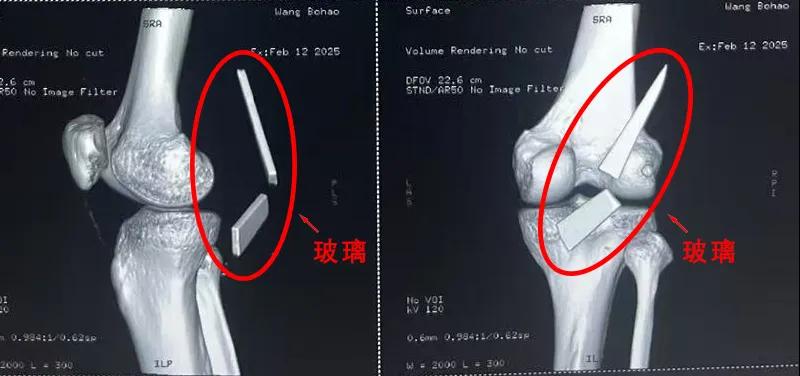

13厘米碎玻璃扎入腿中,漯河醫(yī)專二附院顯微外科緊急“拆彈”......

患者家屬這才開(kāi)始意識(shí)到問(wèn)題的嚴(yán)重性,便帶著孩子到鄉(xiāng)鎮(zhèn)衛(wèi)生院檢查——結(jié)果顯示右膝關(guān)節(jié)后方竟然殘留著兩塊兒鋒利的碎玻璃,測(cè)量后預(yù)估玻璃總長(zhǎng)將近13厘米!

由于玻璃位置毗鄰坐骨神經(jīng)和股動(dòng)脈,一旦刺破股動(dòng)脈,將嚴(yán)重威脅生命。家屬著急萬(wàn)分,想著能否盡快手術(shù)取出碎片,于是慕名來(lái)到漯河醫(yī)專二附院(漯河市骨科醫(yī)院、漯河市立醫(yī)院)手顯微外科(修復(fù)重建骨感染科)。

術(shù)中,馬廣輝醫(yī)生憑借扎實(shí)的理論知識(shí)和嫻熟的顯微外科技術(shù),順利找到深深刺進(jìn)肌肉的兩塊玻璃,肉眼可見(jiàn)玻璃尖端距股動(dòng)脈僅有不到半公分的距離!如果患者再耽誤半天或者再多活動(dòng)幾次膝關(guān)節(jié),小指粗的股動(dòng)脈很有可能被玻璃扎破,后果難以想象。